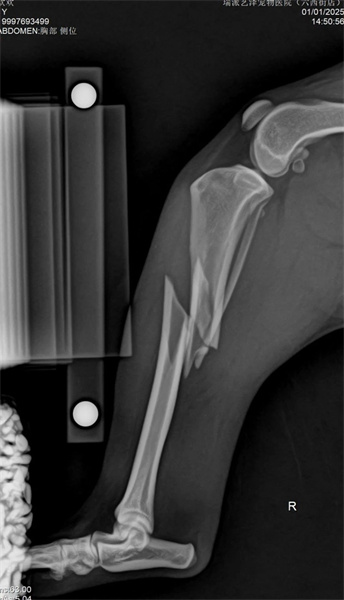

Animal basic information: Country dog, 7kg 1-year-old, cause of fracture: car accident

Right tibial shaft comminuted fracture (closed)